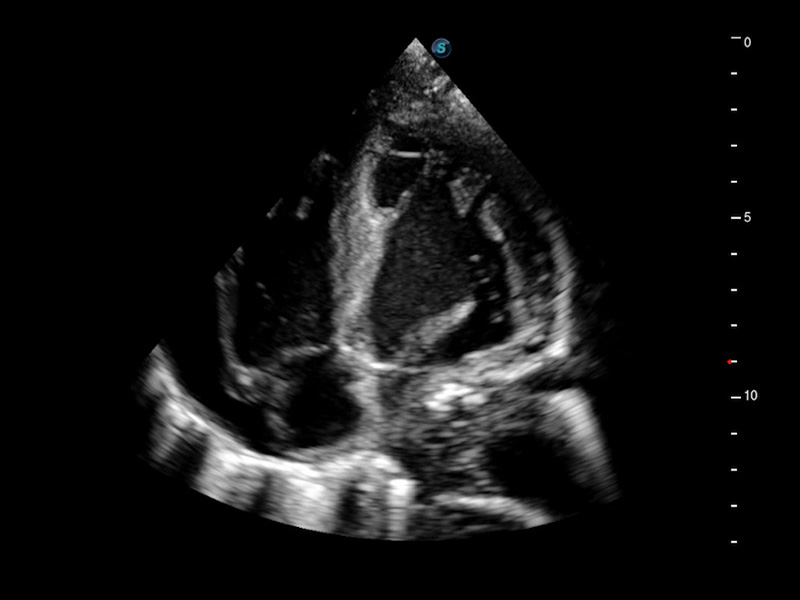

Cardiovascolare avanzato

Si impegna a fornire una soluzione completa per la valutazione cardiaca

Dotato dell'esclusivo trasduttore a cristallo singolo SonoScape e di una tecnologia di elaborazione all'avanguardia, P60 si impegna a ripristinare ogni dettaglio ed elemento per una diagnosi precisa. La nuova analisi quantitativa del miocardio (MQA) fornisce un referto quantitativo approfondito sulle dinamiche del movimento della parete miocardica globale e regionale del ventricolo sinistro, offrendo ai medici una valutazione completa delle funzioni miocardiche.

• Stress Echo

• MQA con analisi della deformazione

• TDI (Tissue Doppler Imaging)

• Opacizzazione VS

• Auto EF